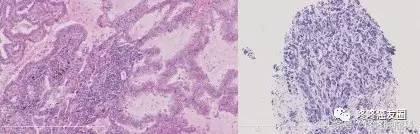

大家都知道肺癌分为两大类——小细胞肺癌和非小细胞肺癌(这个命名方式,是不是很傻)。携带EGFR基因突变的非小细胞肺癌,接受靶向治疗后,一部分会转变为小细胞肺癌,这个现象在接受第一代靶向药的患者中其实不少见,现在也已经报道出现在了小部分服用AZD9291的病人身上——对于这类病友,可以考虑联合AZD9291和适用于小细胞肺癌的化疗(顺铂+VP-16),可能有效果。目前已经有成功的先例,下面就是一个今年3月发表的具体案例(用9291之前是腺癌,耐药以后变成了小细胞肺癌,打了化疗以后,缓解了)。